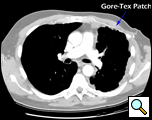

Eleven months later, he presented with a several month history of a painful fixed, firm mass over the pectoral area of the left chest and a smaller mass inferior to this (Figure 1). CT scan demonstrated a new 2 cm nodule in the left upper lobe associated with an anterior chest wall mass six centimeters in size in addition to bilateral new pulmonary nodules (Figure 2). The mass was tethered to the skin and in danger of eroding through it. The patient underwent en-bloc resection of the chest wall and adjacent lung (Figures 3a-c). The resulting defect (Figure 4a) was reconstructed with 2 mm Gore-Tex patch (Figure 4b) and pectoralis major muscle flap (Figure 4c) with primary skin closure (Figure 4d). The pathology revealed metastatic chordoma (Figures 5a-d). The patient recovered well, leaving the hospital on the sixth postoperative day.

The appropriate treatment for chest wall metastases for chordoma is not known due to the rarity of this occurrence. Indications for chest wall metastasectomy include resection for diagnosis, local control, and palliation / prevention of skin ulceration and rarely for cure or as part of a multidisciplinary approach [7]. While radiation therapy is another option for local control, its ability to prevent progression of disease is unpredictable and unknown in the case of chordoma. Once the area of the chest wall has been irradiated, subsequent resection and reconstruction is more difficult and prone to failure [8, 9]. In the presented case, resection was performed for local control, pain relief and to prevent the complications of ulceration, necrotizing infection and bleeding from a tumor eroding through the anterior chest wall. The principles of chest wall resection were adhered to by performing a full thickness en-bloc resection of the mass, reconstruction with a two mm Gore-Tex patch and coverage with a well-vascularized myocutaneous flap.